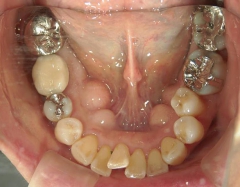

矯正歯科(全顎ワイヤー矯正)治療後

矯正歯科 治療後